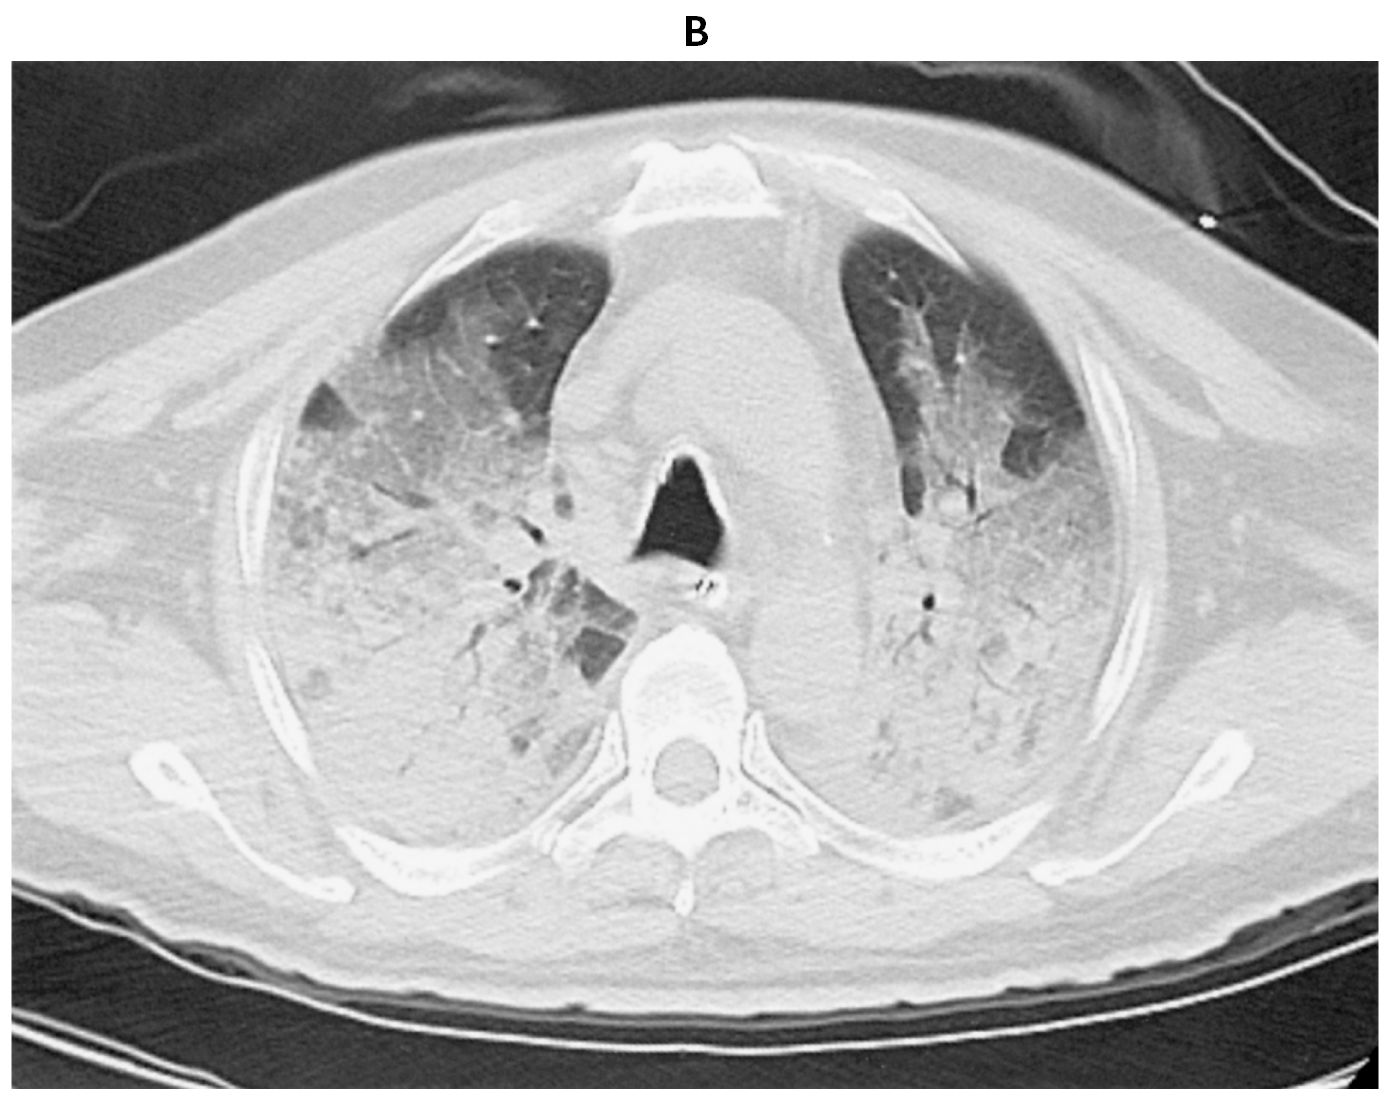

65歳の男性。呼吸困難と意識障害を主訴に救急搬入された。海でシュノーケリング中に溺れすぐに救助されたが,激しい咳嗽と呼吸困難を訴え,意識がもうろうとしており救急要請された。救助30分後の病院搬入時,顔色不良。意識レベルはGCS 8(E3V1M4)。体温37.1℃。脈拍128/分,整。血圧110/84 mmHg。呼吸数28/分。SpO2 84%(リザーバー付マスク10L/分 酸素投与下)。頸静脈の怒張はなく,両側肺でcoarse cracklesを聴取する。心音は整で頻脈,心雑音は聴取されず,下腿浮腫も認めない。血液所見:赤血球468万,Hb 12.2g/dL,Ht 37%,白血球7,100,血小板27万。血液生化学所見:総ビリルビン0.7mg/dL,AST 18U/L,ALT 14U/L,LD 250U/L(基準124~222),γ-GT 15U/L(基準13~64),CK 144U/L(基準59~248),尿素窒素18mg/dL,クレアチニン0.8mg/dL,血糖120mg/dL,Na 146mEq/L,K 3.6mEq/L,Cl 113mEq/L。CRP 0.1mg/dL。動脈血ガス分析(リザーバー付マスク10L/分 酸素投与下):pH 7.30,PaCO2 53 Torr,PaO2 50 Torr,HCO3 15mEq/L。心電図は洞性頻脈。ベッドサイドで行った心エコー検査では壁運動は正常で,心嚢液の貯留も認めない。救急室で気管挿管後,気管チューブから海水が吸引された。挿管後に撮影した胸部エックス線写真(A)と胸部単純CT(B)とを下に示す。

無料会員登録していただくと、実際の解説をすべて見ることができます。急性の呼吸困難を主訴とする疾患としては,喉頭浮腫,気道異物,自然気胸,気管支喘息,慢性閉塞性肺疾患の急性増悪などの呼吸器疾患,心不全(急性,慢性の急性増悪),肺血栓塞栓症などの循環器疾患が代表的である。この症例では呼吸器感染症と心不全が疑われるが,胸部エックス線写真は肺炎像というよりも両心不全を示唆する所見を示している。診断:心不全(両心不全)(Nohria分類wet and warm) 選択肢考察 ×a 強い呼吸困難,胸痛などにより安静が保てない場合には,血管拡張による前負荷軽減と,交感神経抑制による心筋酸素消費量の減少を目的としてモルヒネを使用する。この症例ではモルヒネが必要となるほどの興奮状態ではない。